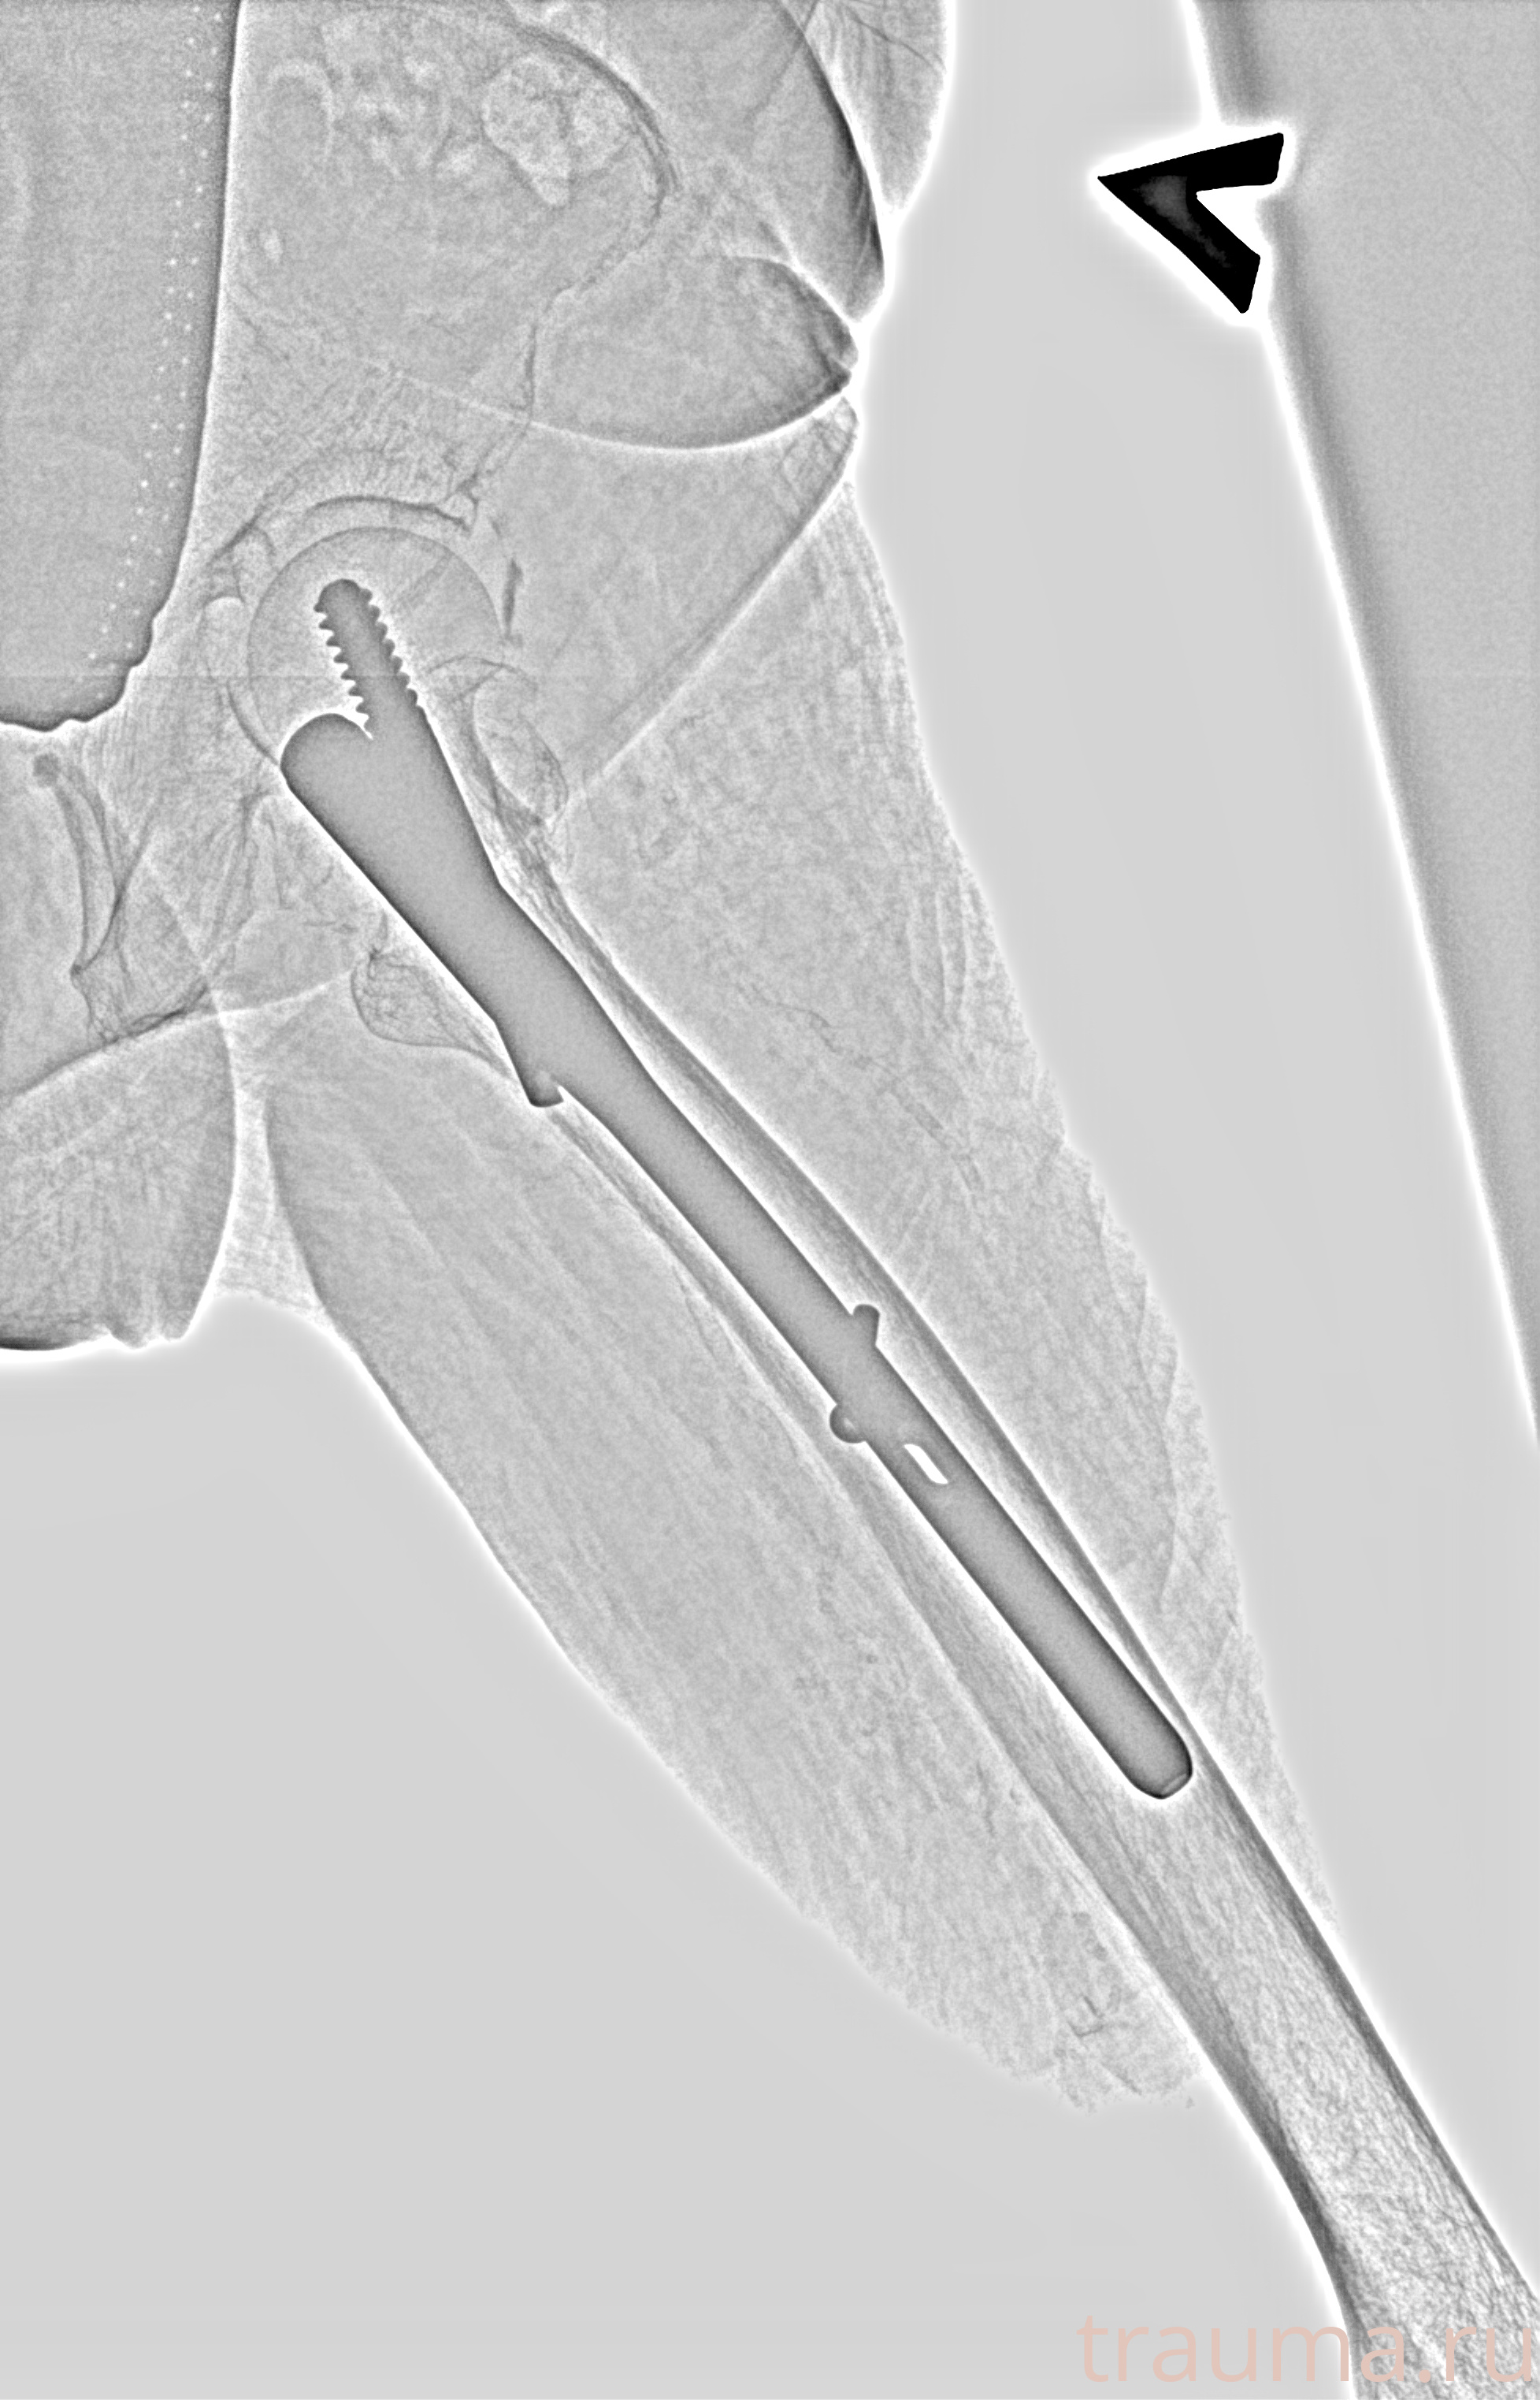

Рентгенограммы

Рентген на дому: по вашему адресу приезжает врач-рентгенолог, травматолог-ортопед с мобильным рентгеновским аппаратом, проводит диагностику травмы или заболевания, делает необходимые рентгенограммы, дает рекомендации по дальнейшему лечению. Получить качественные снимки в домашних условиях возможно благодаря уникальной методике, разработанной МосРентген Центром для института  Склифосовского